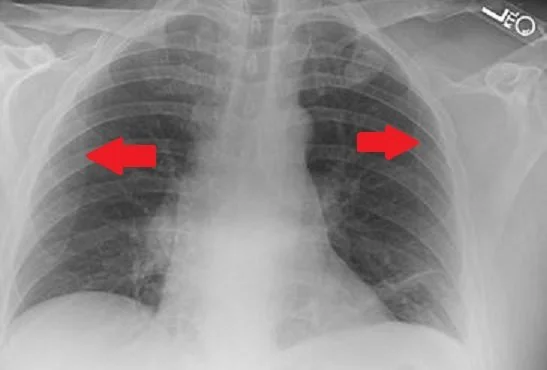

Scapulothoracic dissociation –these are more likely to occur with high velocity injuries commonly motorcycle riders who are thrown off their vehicles with the arm caught under a handlebar. In these injuries vascular damage occurs often with the brachial plexus injury. They can be seen on CXR by comparing the distance of the scapula from the spine.

measure the distance from the spine to the scapula to find a scapulothoracic dissociation. In this image more of the scapula projects over the chest on the R than the L